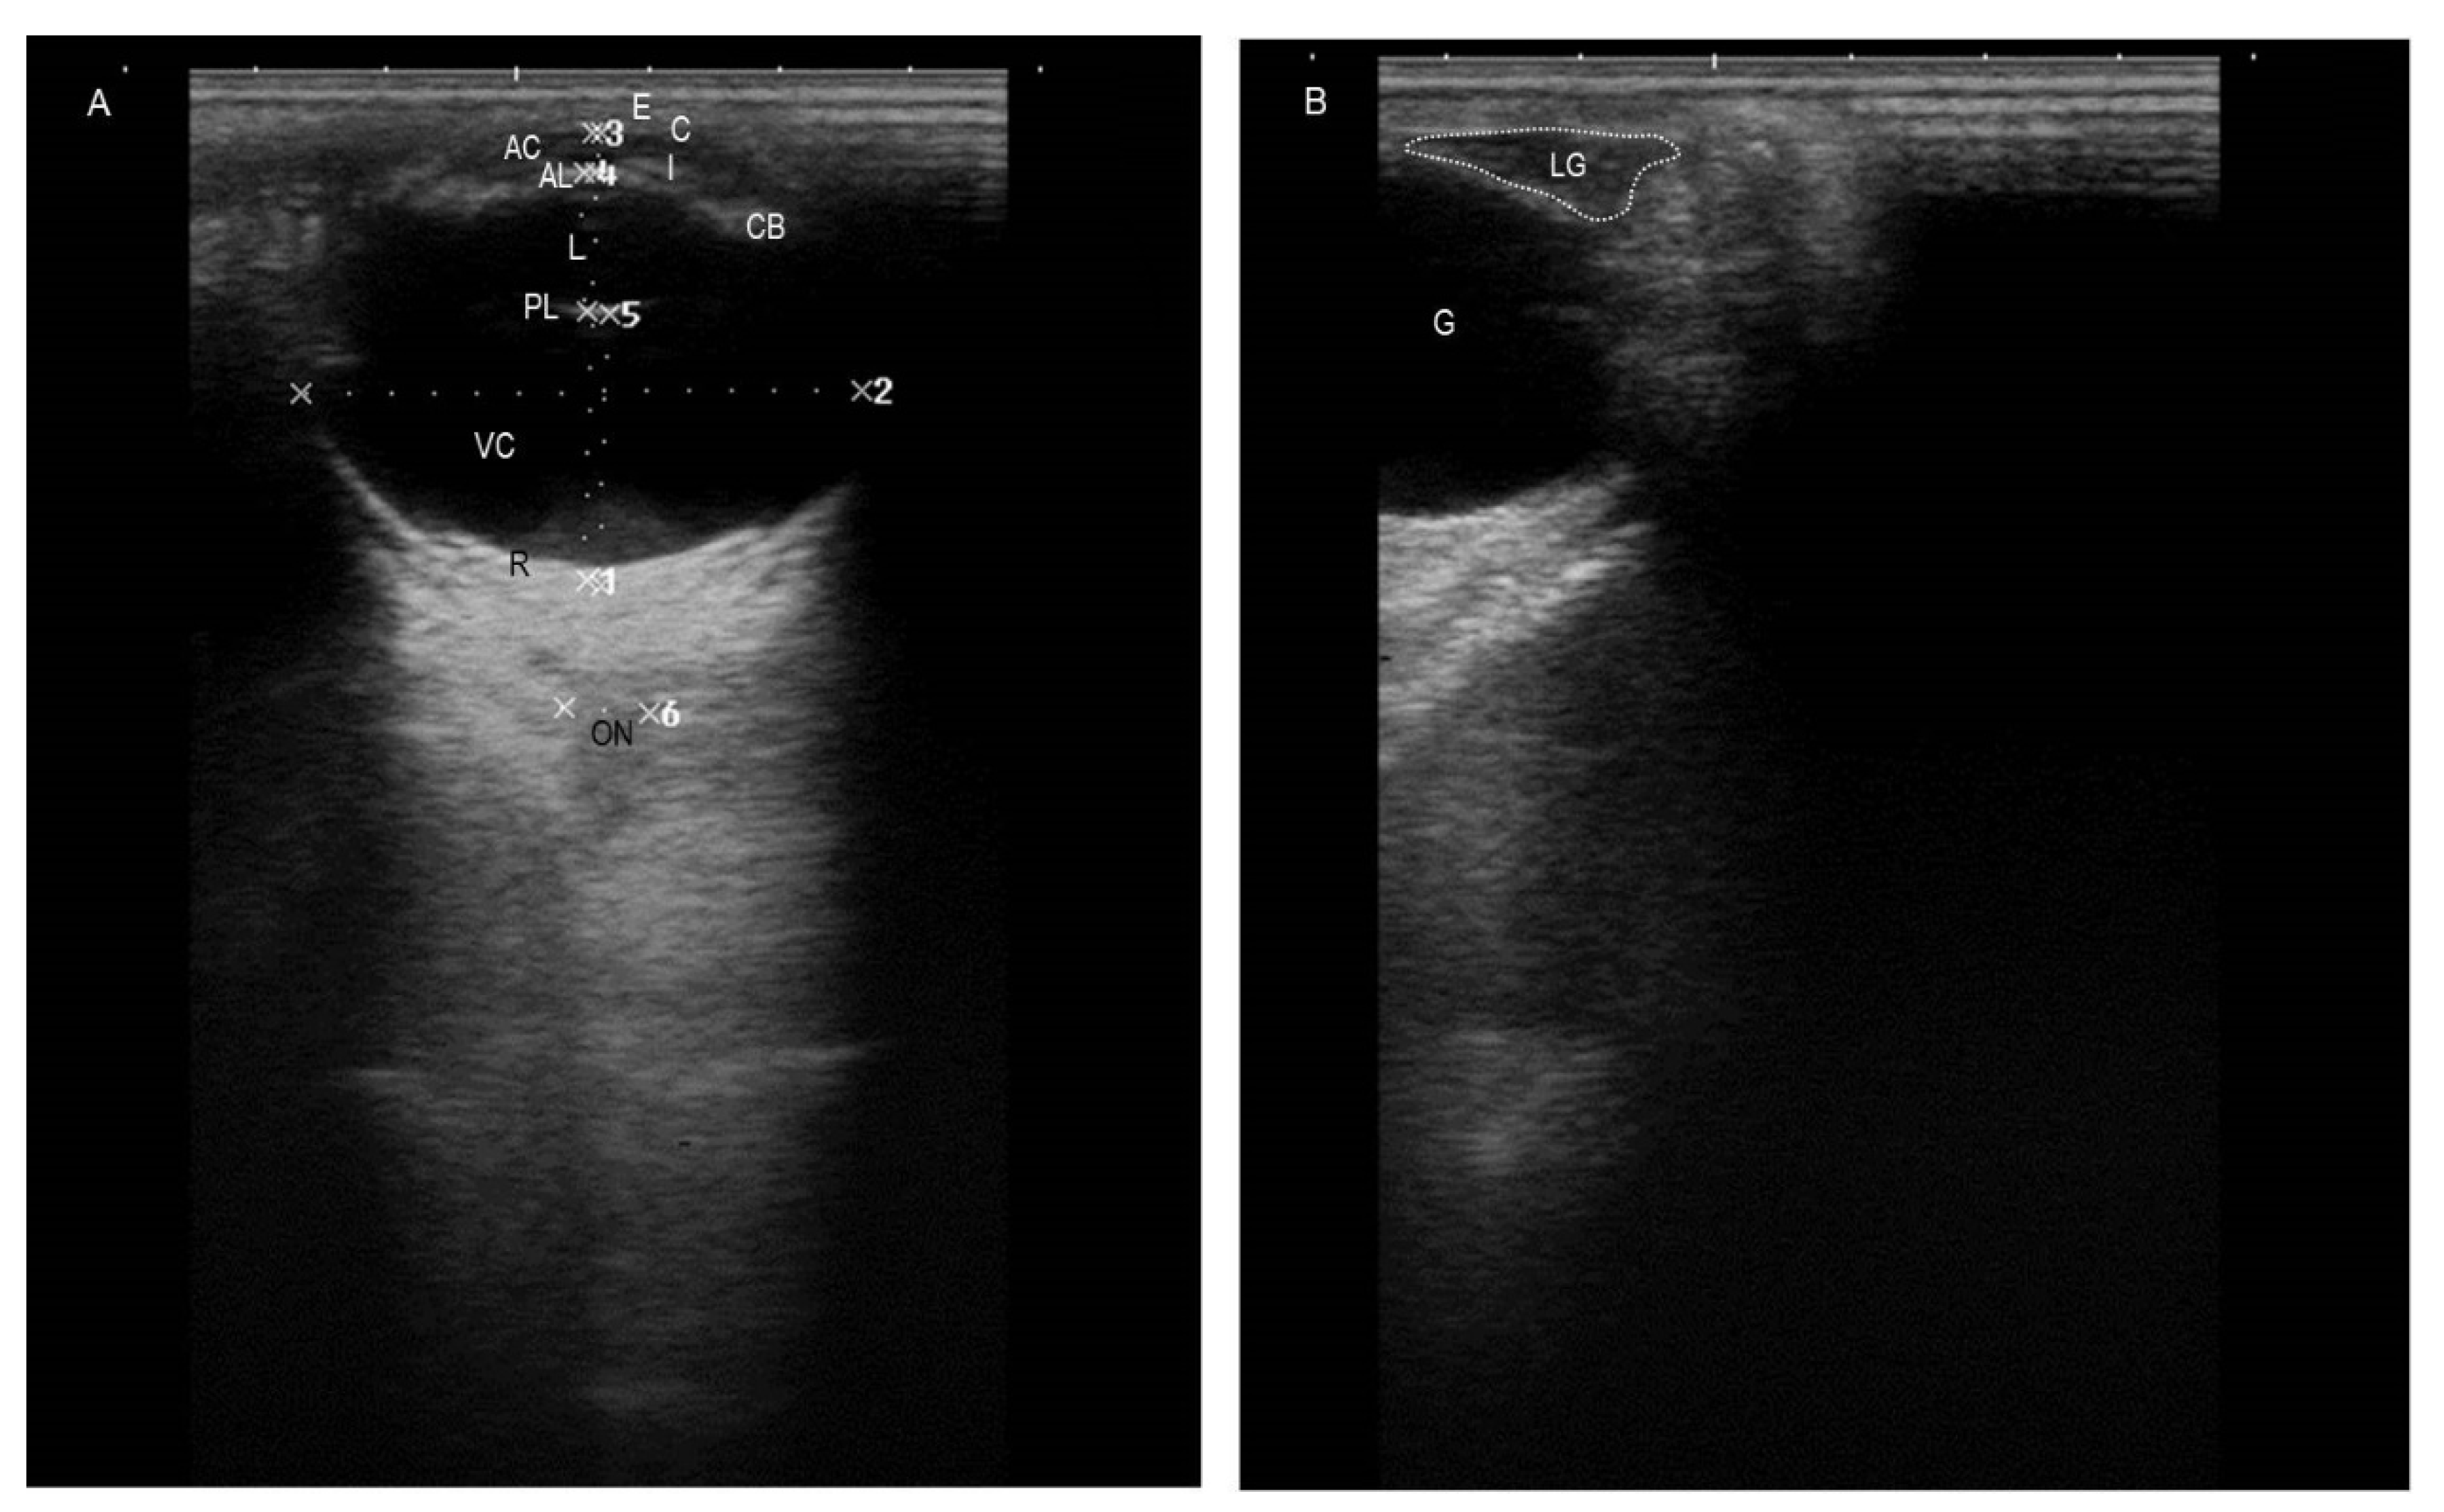

3.1. Ultrasonographic Findings

| Ultrasonography | Axial globe length (AGL) | 30.4 | 36.1 | 33.7 (1.7) |

| Globe diameter (GD) | 35.7 | 43.1 | 39.8 (2.1) | |

| Lens thickness (LT) | 10.1 | 12.5 | 10.8 (0.7) | |

| Anterior chamber diameter (ACD) | 2.5 | 3.9 | 3.2 (0.5) | |

| Vitreous chamber diameter (VCD) | 16.3 | 21.9 | 19.3 (1.6) | |

| Lacrimal gland length (LGL) | 14.3 | 20.1 | 16.9 (1.6) | |

| Lacrimal gland diameter (LGD) | 5.1 | 6.4 | 6.1 (0.3) | |